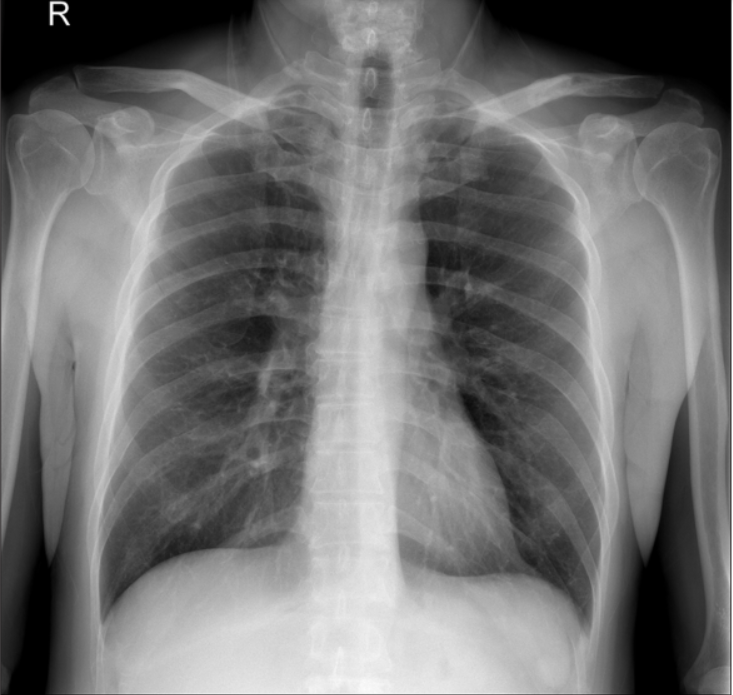

肩部正位平片显示锁骨中轴线状骨折,肩锁关节间隙无明显增宽,锁骨外侧端无明显增高